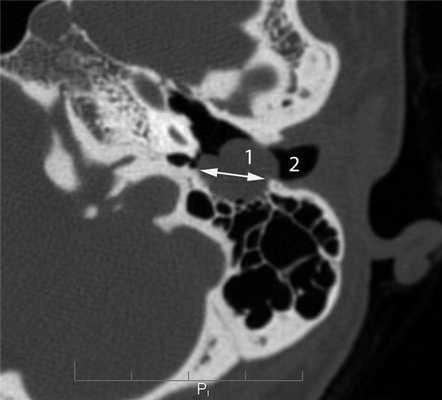

КТ-симптоматика параганглиомы или гломусной опухоли височной кости, редко встречающейся у детей, включает нарушение пневматизации полостей среднего уха в сочетании с костной деструкцией (рис. 7, а). Рисунок 7. Гломусная опухоль. а — аксиальная проекция правой височной кости. В пирамиде височной кости определяется объемное образование, вызывающее разрушение стенок ямки луковицы яремной вены (1) и канала внутренней сонной артерии (2). Поскольку параганглиома исходит из яремного и, реже, каротидного гломуса, ее отличительным КТ-признаком является деструкция стенок ямки луковицы яремной вены и канала сонной артерии [5—7]. В отличие от злокачественных опухолей, параганглиома активно накапливает контрастный агент при внутривенном введении в артериальную фазу (рис. 7, б). Рисунок 7. Гломусная опухоль. б — коронарная проекция левой височной кости, внутривенное болюсное контрастирование, артериальная фаза. В барабанной полости определяется опухоль (1), активно накапливающая контрастный агент. Практически одинаковая интенсивность накопления контрастного вещества в ткани опухоли и во внутренней сонной артерии (2).